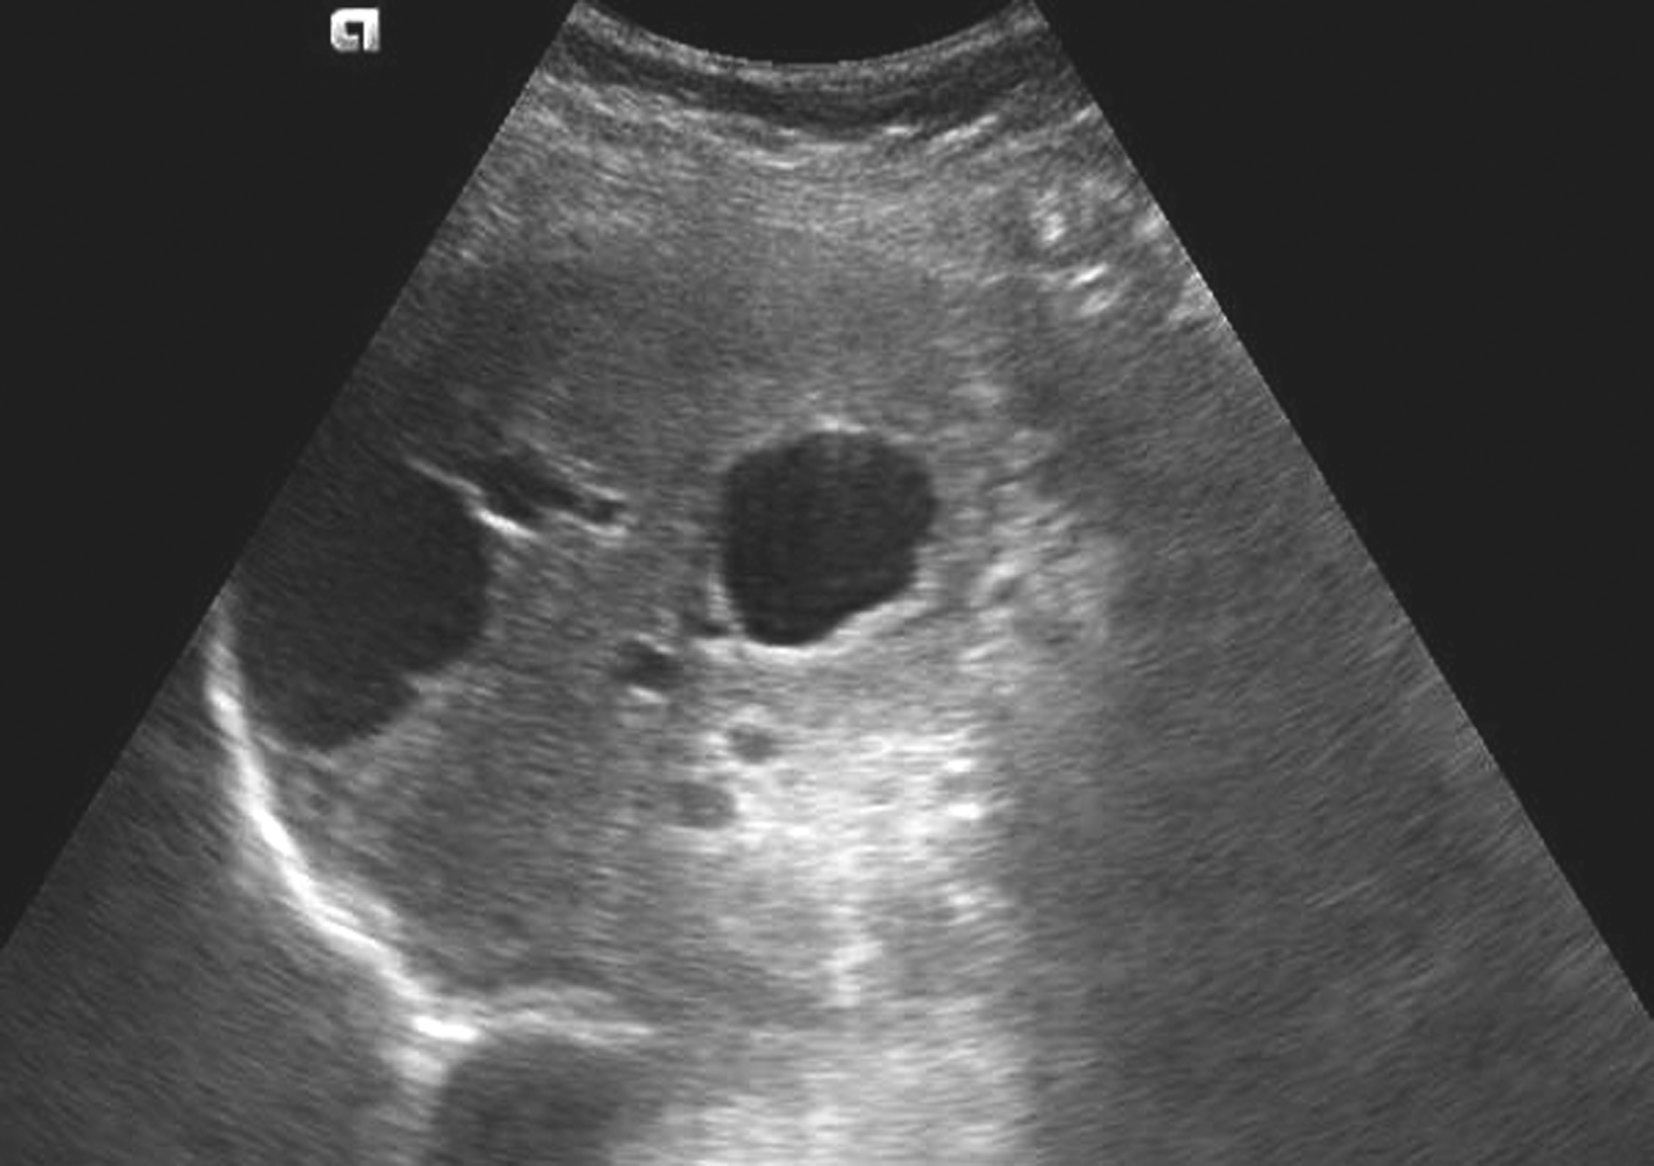

门静脉海绵样变性是指门静脉主干或分支完全、部分栓塞,而后由其侧支静脉形成或管腔的再通所致。引起门静脉阻塞的常见原因是癌栓,其次是血栓。门静脉右支发生率高。临床上主要表现为门静脉高压症状,如脾大、腹水甚至胃肠道静脉曲张性出血。

【声像图表现】

(1)灰阶超声:

肝门区结构紊乱,肝外门静脉周围或管腔内可见多条弯曲成团的血管,呈蜂窝状或网格状无回声区结构,在结构紊乱的肝门部仔细辨认可见管腔狭窄、壁增厚回声增强的门静脉管道,管腔内可见癌栓或血栓,部分可压迫胆道系统造成肝内外胆管扩张。可出现继发门静脉高压声像图改变,如脾肿大、脾静脉及肠系膜上静脉增宽,严重者可见腹水。

(2)彩色多普勒血流显像:

在肝门区蜂窝状或网格状无回声区结构内充满色彩暗淡的彩色血流信号;门静脉狭窄者于门静脉内探及少许连续性彩色血流通过,其周围蜂窝状液性无回声区呈红、蓝相间的不连续彩色血流信号;完全闭塞或栓子充填的门静脉内则无彩色血流信号显示;如图5-21-26所示。

(3)频谱多普勒表现:

门静脉海绵样变性区域于蜂窝状或迂曲的管状无回声区内均可探及门静脉样连续状低速血流频谱;如图5-21-27所示。

图5-21-26 门静脉海绵样变性二维灰阶图像

图5-21-27 门静脉海绵样变性彩色多普勒图像